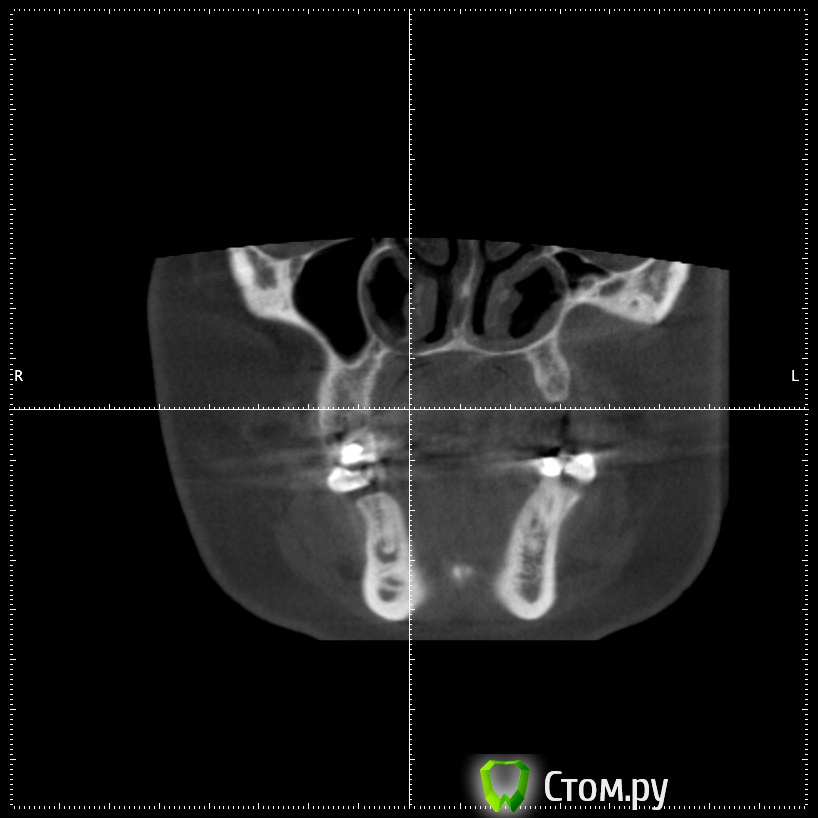

stommm Опубликовано 17 сентября, 2014 Поделиться Опубликовано 17 сентября, 2014 Всем доброго времени суток) Ко мне обратилась пациентка с жалобами на отсутствие зубов во втором сегменте. Сделала кт. Честно говоря такого кт я еще не видел.Что это, господа, вариант нормы или признак патологии? Встречалось ли подобное в вашей практике? Планирую нарастить по ширине и имплантировать, без синуса. Ссылка на комментарий

Bier Опубликовано 18 сентября, 2014 Поделиться Опубликовано 18 сентября, 2014 тут просто пазуха заросла костью, природа сделала синуслифтинг )) 2 Ссылка на комментарий

stommm Опубликовано 18 сентября, 2014 Автор Поделиться Опубликовано 18 сентября, 2014 По данным литературы, в 7-10% случаев может наблюдаться асиметрия пазух (пневматизированная/склерозированная)Я думаю здесь не просто одна пазуха более пневматизированная чем иная. Полость носа тоже кажется довольно несимметричной. тут просто пазуха заросла костью, природа сделала синуслифтинг ))А то что ширина самих пазух отличается сильно, это нормально? Ссылка на комментарий

Alexey Doc Опубликовано 18 сентября, 2014 Поделиться Опубликовано 18 сентября, 2014 Гипоплазия левой гайморовой пазухи. У самого было 2-е похожих пациентов 2 Ссылка на комментарий

dr-krasnov Опубликовано 6 октября, 2014 Поделиться Опубликовано 6 октября, 2014 Гипоплазия левой гайморовой пазухи. У самого было 2-е похожих пациентов Верный ответ. 1 Ссылка на комментарий